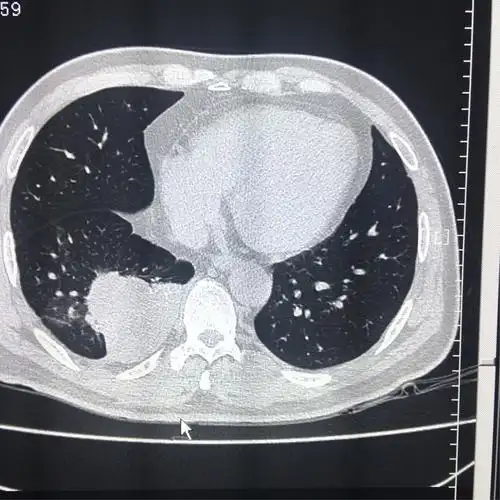

肺隔离症